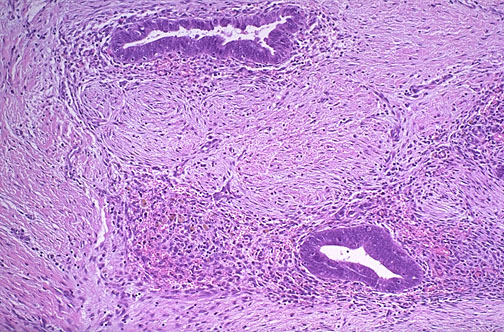

Endometrial glands and stroma are seen at high magnification in the wall of the colon. Endometriosis is symptomatic during reproductive years when patients may present with dysmenorrhea, pelvic pain, and infertility.